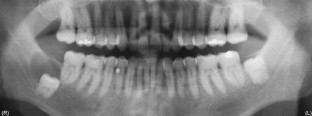

Fig. 4